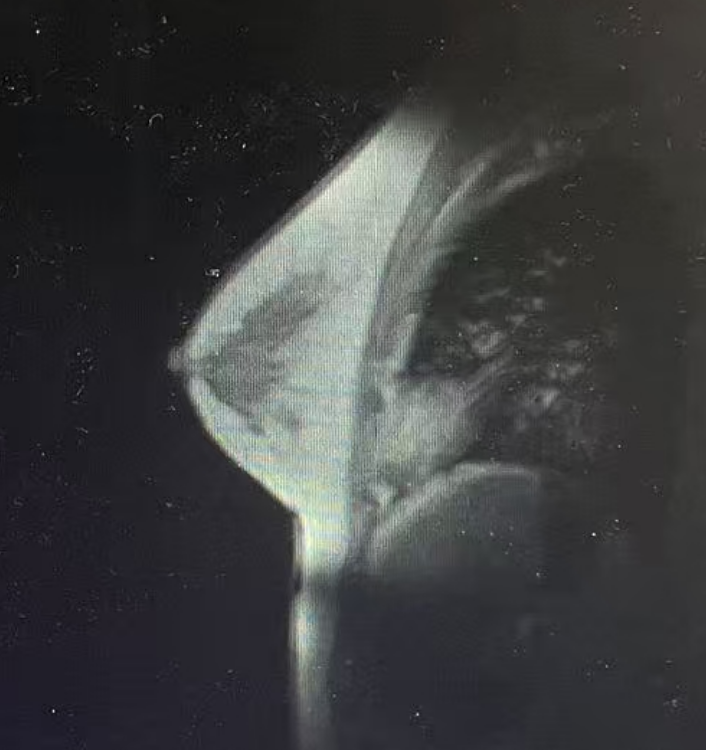

·病理

(右乳肿块穿刺病理):浸润性乳腺癌,非特殊类型(浸润性导管癌),Nottingham分级:2级,未见明确脉管内癌栓及神经侵犯。免疫组化结果:ER(约2%弱+),PR(约5%弱+),Her-2(3+),Ki67(约50%+)。

图5穿刺活检结果